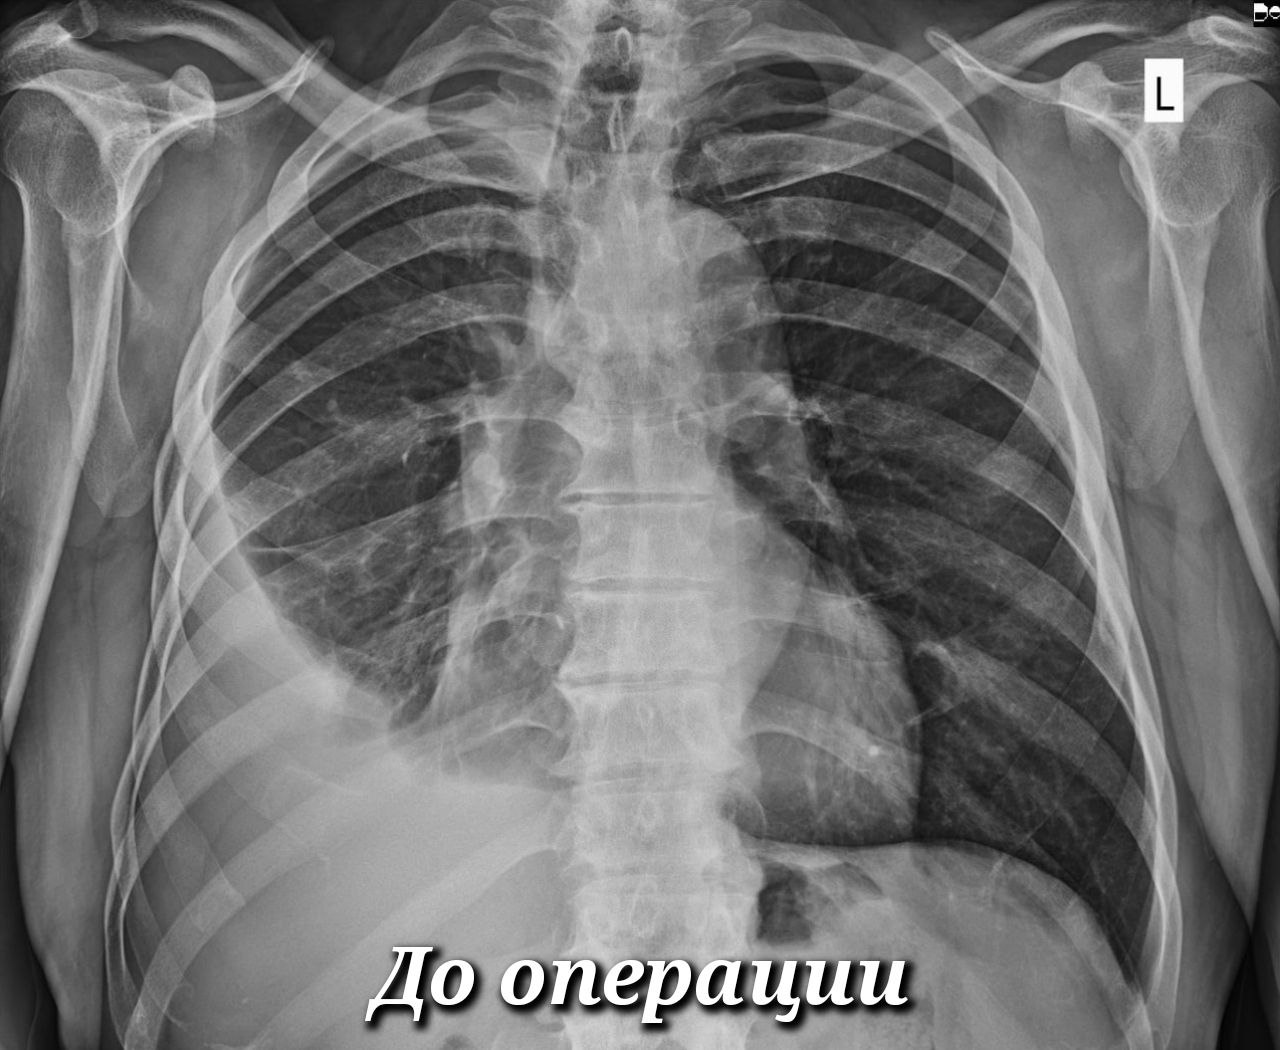

Правда, ситуации разные. Если с экрана нам рассказывают о последствиях травмы грудной клетки, то врачи травмбольницы имеют дело с грозным заболеванием, при котором плевральная полость заполняется гнойным содержимым. Из-за этого лёгкое сдавливается и не может полноценно участвовать в дыхательном процессе. Больные испытывают постоянную дыхательную недостаточность, у них развивается системная воспалительная реакция, интоксикационный синдром, в худшем случае – сепсис и полиорганная недостаточность.

Эмпиема плевры – вторичная патология, возникает как осложнение, в том числе, после вирусных и бактериальных пневмоний. За последние два года торакальные хирурги Сургутской травмбольницы внедрили и поставили на поток высокотехнологичную малоинвазивную методику оперативного лечения этого заболевания. Она пришла на смену тяжелым обширным вмешательствам на грудной клетке с длительным и сложным послеоперационным ведением больных.

-Во время операции наша задача избавиться от очага инфекции и затем проконтролировать, чтобы лёгкое расправилось и приняло своё анатомическое положение. Оно сразу включается в работу и начинает выполнять свою функцию. Послеоперационный период предполагает активное дренирование плевральной полости с периодическими санациями. В среднем лечение такого больного в стационаре сегодня занимает две недели. После открытых операций больные находились у нас по 2-3 месяца и даже после выписки до полугода оставались с множественными дренажами, - объясняет Ринат Рахметов, хирург окружного Центра торакальной хирургии на базе Сургутской травмбольницы.

Очередная такая операция на днях успешно выполнена 68-летнему пациенту. Немногим раньше её благополучно перенесла 30-летняя женщина. Врачи отмечают, что эта категория больных разновозрастная. Многие пациенты не относятся к группам риска и имеют нормальный иммунитет. Это активные, работающие люди, которым важно быстрее вернуться в строй.